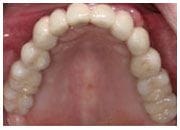

治療後